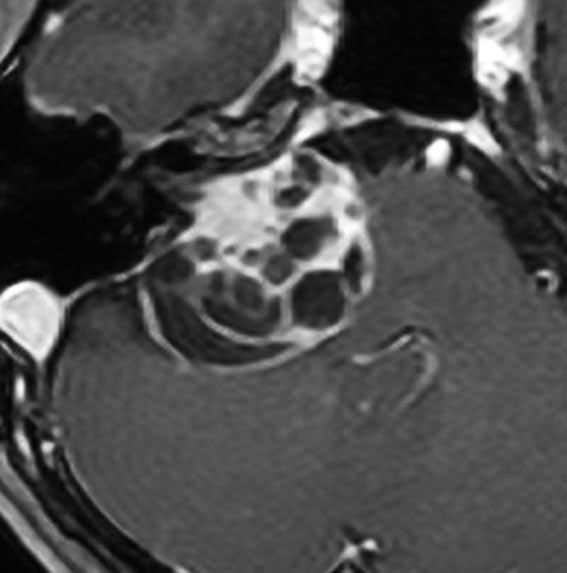

大きなのう胞性聴神経腫瘍です。いくつかの袋が重なって腫瘍を形成しています。橋や延髄(脳幹部)が変形して,第4脳室がつぶれて閉塞しています。袋の周りが白く線状に造影されているのですが,この袋の壁だけに腫瘍細胞がありますから,これを剥がすように摘出します。顔面神経が薄くなって袋の壁にくっついているのですが,袋を破ってくしゃくしゃにすると顔面神経の位置が変わってしまって,顔面神経を損傷することがあるので要注意です。のう胞性聴神経腫瘍の方が顔面神経麻痺の後遺症の頻度が高いという報告もあるくらいです。この患者さんは迷走神経と舌咽神経の圧迫も強くて,ご飯を飲み込むことが難しくなっていました(嚥下障害)。